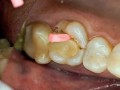

Augmentacja boczna wąskich wyrostków zębodołowych z…

Damian Dudek, Maciej Jagielak, Aldona Chloupek, Oliwia Warmusz, Edyta Reichman-Warmusz